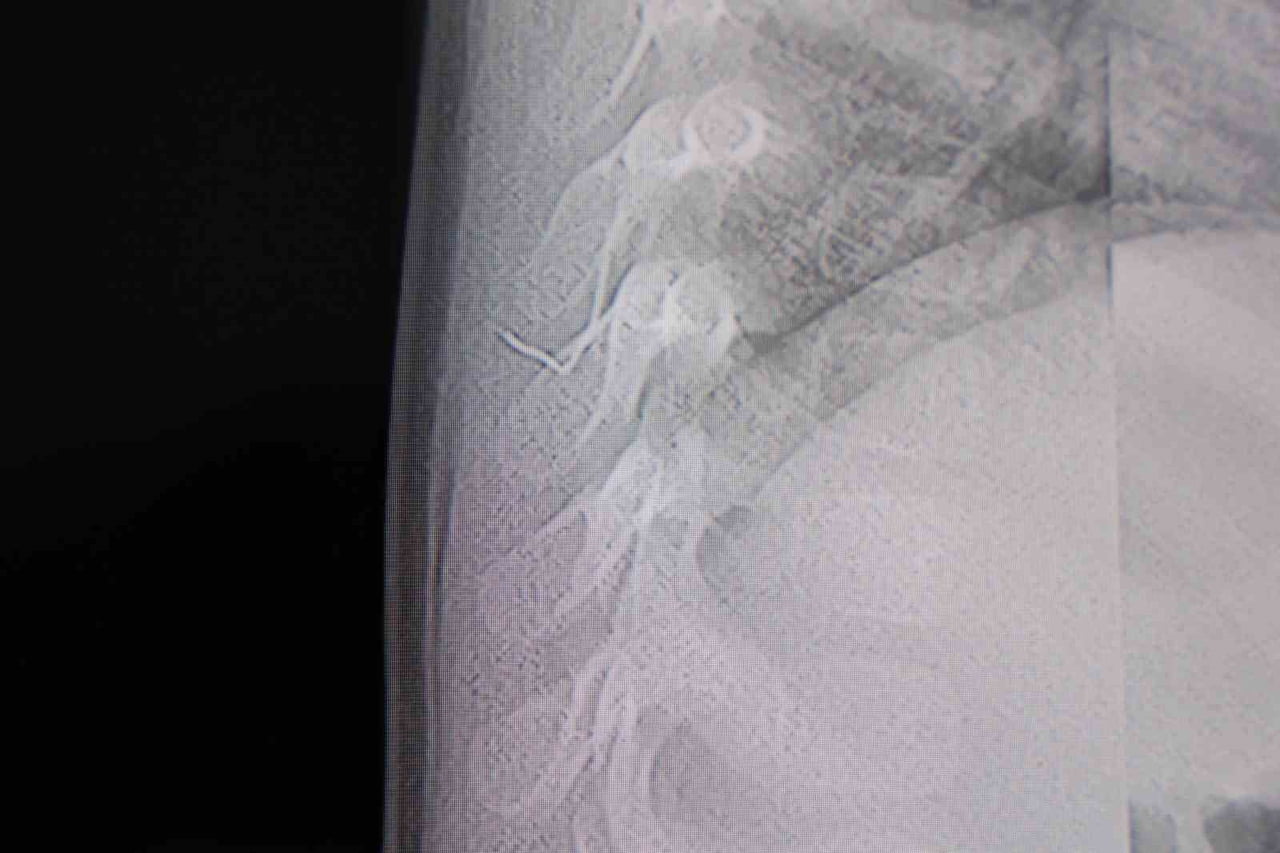

HG Hospital Beyin ve Sinir Cerrahisi Uzmanı Prof. Dr. İdris Altun tarafından yapılan tetkiklerde, yabancı cismin cilt altında, omurilik kanalına çok yakın bir bölgede olduğu ve akciğer zarına doğru ilerlediği belirlendi.

Hasta, genel anesteziye alınmadan, lokal anestezi ve sedasyon eşliğinde ameliyata alındı. Yapılan müdahalede yabancı cisim tamamen çıkarıldı. Çıkarılan cismin ince zımba teline benzer metal bir tel olduğu ve yaklaşık 2 santimetre uzunluğunda bulunduğu tespit edildi. Operasyonu takiben hasta aynı gün taburcu edildi.

"Sırtında yabancı bir cisim olduğu söylenmiş ancak çıkarılamayacağı ve 8 yaşına kadar beklenmesi gerektiği ifade edilmişti. Bize başvurduğunda yaptığımız tetkiklerde, cilt altında, omurilik kanalına çok yakın ve akciğer zarına doğru ilerleyen bir yabancı cisim tespit ettik. Hastamızı tamamen uyutmadan, lokal anestezi ve sedasyon eşliğinde müdahale ederek lezyonu tamamen çıkardık. Çıkardığımız cismin ince zımba teline benzer, yaklaşık 2 santimetre uzunluğunda metal bir tel olduğunu gördük. Bu yabancı cisim alınmasaydı, bölgede enfeksiyon gelişebilirdi. Enfeksiyon sonucu omurilik kanalında ciddi hasarlar oluşabilir, çocuk büyüdükçe cismin hareket etmesine bağlı olarak omurilikte zedelenmeler meydana gelebilirdi. Ayrıca yana doğru ilerleyerek akciğer zarına ve akciğere batma riski vardı. Bu da enfeksiyona ve ilerleyen süreçte tümörle karışabilecek tablolara neden olabilirdi. Şu an hastamız gayet sağlıklı. Gerekli kontrolleri yaptık ve aynı gün taburcu ettik"